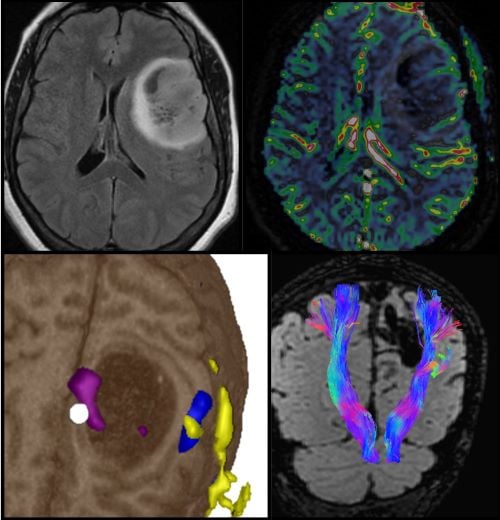

Neuroradiology →

The mission of the Neuroradiology Fellowship Program is to provide an in-depth, comprehensive neuroimaging experience, and expose fellows to research, quality assurance methods and leadership initiatives. Fellows train in a supportive, collegial, tertiary care hospital setting that enables them to provide outstanding health care, contribute to advancing medical knowledge and achieve their career goals.